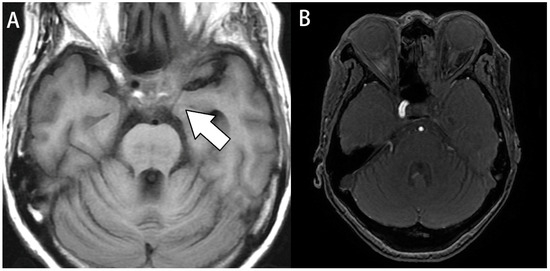

Figure 2.

Image study of case 8. A 61-year-old woman with a history of diabetes presented with ptosis, double vision, extraocular muscle limitation, blurred vision, and fever. (A) Axial T1- weighted images. Fluid accumulated over the left cavernous sinus, causing luminal narrowing of the left carotid artery (white arrow). (B) Magnetic resonance angiography (MRA). MRA revealed occlusion in the left internal carotid artery.